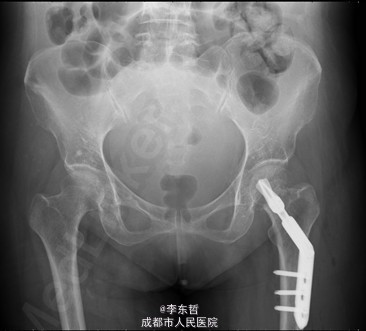

积极完善术前检查及准备后行左股骨颈骨折闭合复位DHS内固定术

随访无特殊